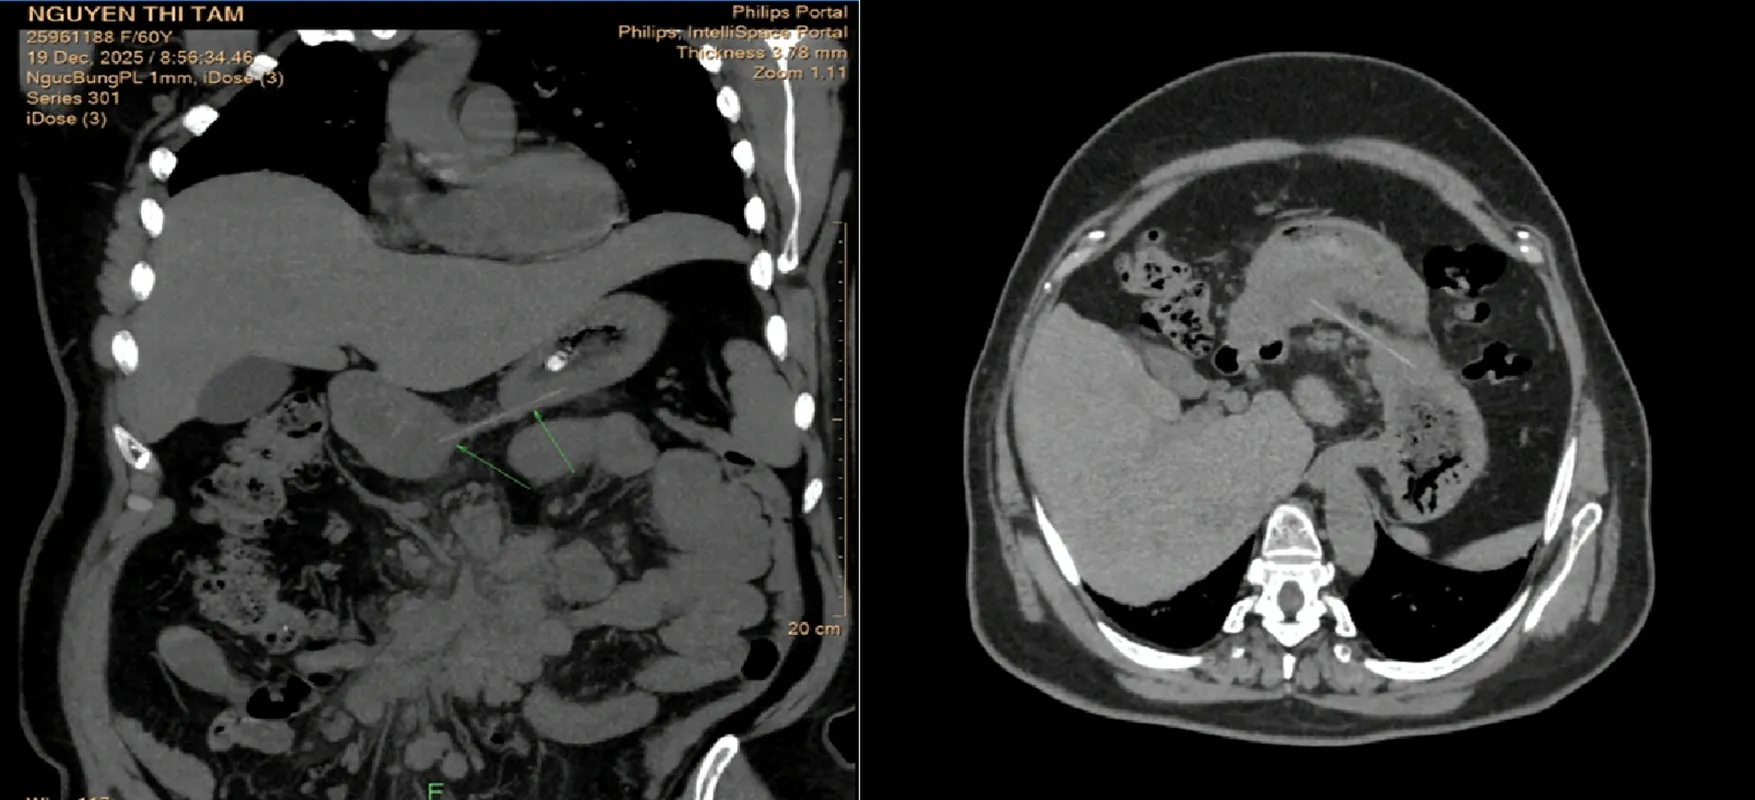

Một bệnh nhân nam, 75 tuổi cũng đã nhập viện trong tình trạng đau bụng dữ dội, sốt cao. Bác sĩ chẩn đoán viêm phúc mạc toàn thể do thủng trực tràng trên. Nguyên nhân gây ra là do mảnh xương cá đã nuốt phải 4 ngày trước.

Bệnh nhân đã chịu đựng đau trong 4 ngày, dẫn đến biến chứng nặng nề nhất là viêm phúc mạc (nhiễm trùng ổ bụng lan tỏa). Vị trí thủng là tại trực tràng (đoạn cuối ruột), cho thấy xương cá đã đi qua gần như cả hệ tiêu hóa trước khi gây thủng.